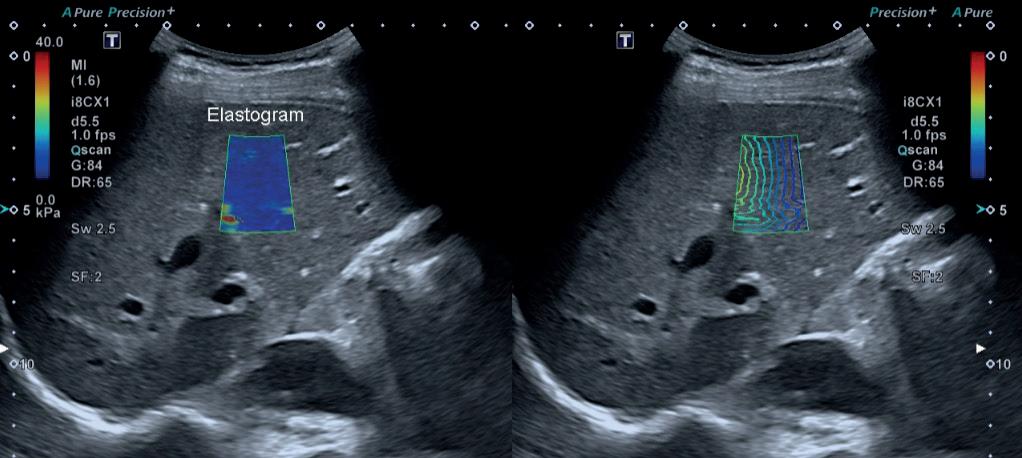

Transabdominal ultralydundersøkelse har lenge vært et helt sentralt diagnostisk hjelpemiddel ved både akutte og kroniske leversykdommer. Undersøkelsen utføres relativt raskt, og er helt ufarlig. Dagens billedkvalitet er svært god, og moderne apparater har innebygde algoritmer som automatisk optimaliserer bildet uten at brukeren trenger vesentlig teknologisk kompetanse. Doppler-funksjon for vurdering av vaskulære strukturer er alltid tilgjengelig, og stadig flere apparat har integrert programvare for elastografi av lever.

sykdom (MASLD), alkoholrelatert leversykdom (ALD) eller en blanding (MetALD). Ved ultralyd er det lett å påvise steatose med høy grad av sikkerhet, således er undersøkelsen et viktig diagnostikum for disse etiologier. Som kjent er det kun en liten andel som utvikler leverfibrose på denne bakgrunn, spesielt ved (MASLD), og den initiale utredning har derfor som mål å avklare hvilke pasienter som er i ferd med å utvikle leverfibrose, og i hvilken grad. Her er elastografi et essensielt verktøy; verdier under 8 kPa tilsier svært lav risiko for avansert leverfibrose, slik at disse pasientene ikke trenger oppfølging fra spesialisthelsetjenesten. Bestemmelse av fibrosestadium er selvsagt viktig ved alle kroniske leversykdommer, og i tillegg til elastografi kan man også vurdere spesifikke ultralydfunn som kan gi mistanke om avansert leverfibrose selv om det ikke foreligger manifest cirrhose.